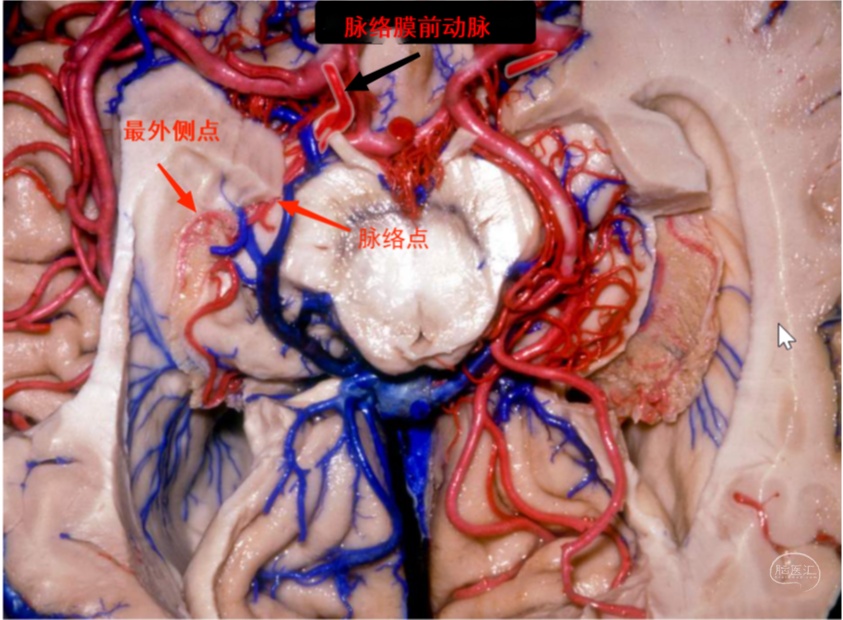

脉络膜前动脉自颈内动脉床突上段后壁发出,发出位置位于后交通动脉发出点与颈内动脉分叉部之间,以脉络点(Plexal point)为界分为脑池段和脉络丛段。脉络点为脉络膜前动脉进入脉络裂的部位,在Rhoton解剖中又称为下脉络点(inferior choroidal point)。如何理解和识别脉络点呢?且看以下分解。

图3 下面观 右侧脉络膜前动脉于脉络点进入脉络裂后继续向外侧走形,达到最外侧点后向后上呈“C”形沿脉络丛走形。

图5 内侧面观 脑池段呈S形,其后部在沟回后段向后并略向下进入脉络点,然后向外并略向上进入颞角,形成一典型的转折,这是DSA上识别脉络点的典型标志。脉络丛段在颞角内沿脉络丛向后内上走形。